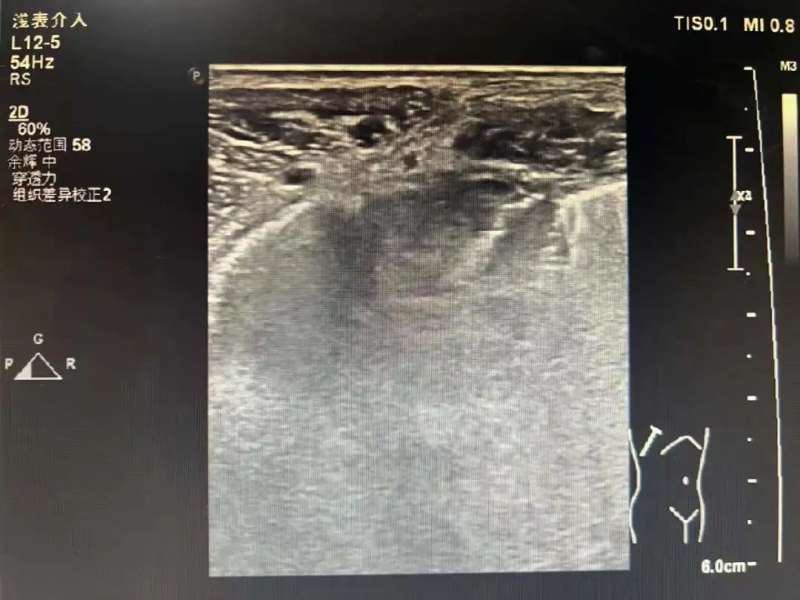

为进一步诊断病情,3月17日在陈勇辉超声引导下,超声医学科蒋朝霞主任医师为林伯伯进行肺肿瘤穿刺活检。超声引导下以右肺肿瘤最清楚处为目标,用穿刺针沿着引导线刺入,通过针尖穿越肿瘤触发活检枪进行活检。穿刺后,林伯伯无不适。我院超声医学科成功完成穿刺活检,为患者进行专科治疗做“最强辅助”,充分体现了我院超声医学科能力水平的综合提升,让患者能就近就医、就近诊断,为患者减轻看病就医经济负担和解决奔波劳碌的问题。

穿刺活检使用特殊的穿刺针,专用的穿刺设备,在彩超或者CT甚至是磁共振的定位和引导之下,将穿刺针刺入人体的病变部位,在特定的位置,通过穿刺针切割一定量的病变组织,将这些组织制作成标本,经过一些特殊的处理后,进行病理学的诊断,来确定这个病变组织究竟是“良”是“莠”,以制定诊疗方案。